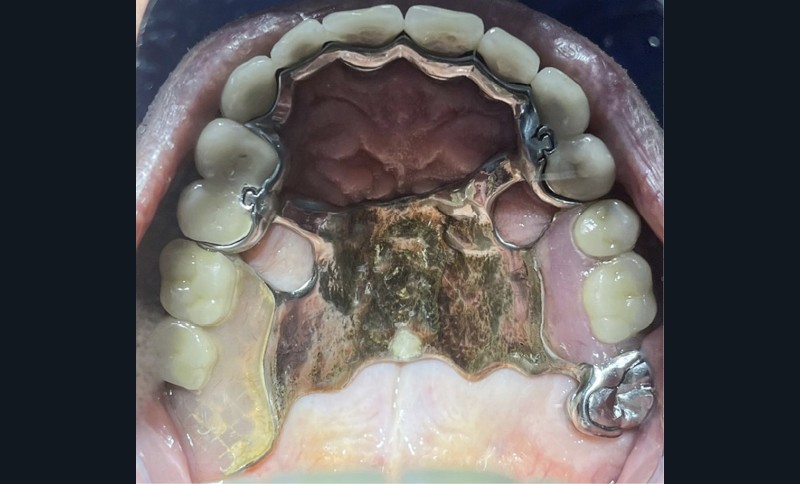

à l’examen endo-buccal, le patient présente un édentement de classe II de Kennedy modification 1, compensé par une prothèse amovible partielle composite en cobalt-chrome (fig. 1a et 1b). On note la présence de glissières de semi-précision parallèles PDC II (Afinor) entre 14-15 et entre 23-24, apportant guidage, stabilisation, sustentation et rétention par effet de coin. Au niveau mandibulaire, le patient présente un édentement de classe III modification 2 avec des crêtes de classe 3 selon la classification de Cawood et Howell, associées à une muqueuse ferme et adhérente (fig. 1c). L’insertion du frein lingual et labial, ainsi que des brides musculaires sont à distance. On note la présence de couronnes fraisées en 38 et en 46, l’absence de lésions apicales actives à l’examen radiographique (fig. 2), et une mésioversion de la 38 prenant la place de la 37.